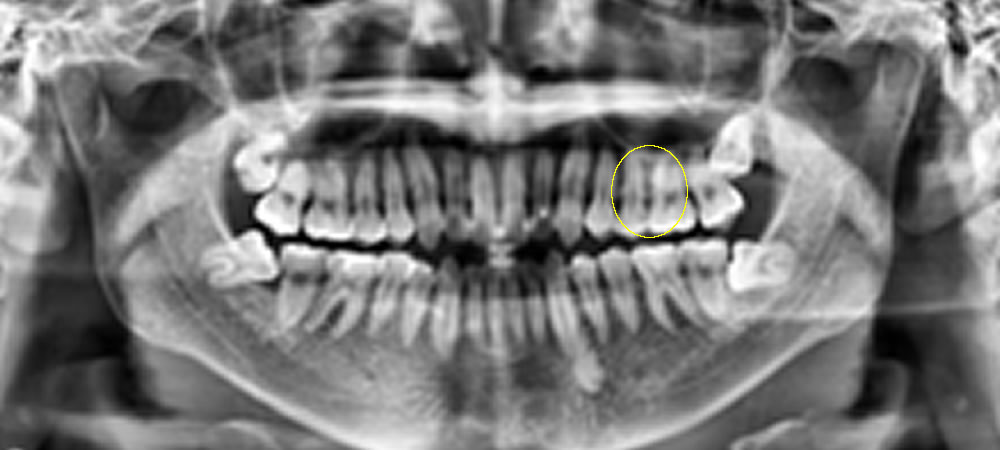

診査とレントゲン検査の結果、左上の奥歯(左上5番)の歯と歯の間に虫歯が認められました。歯と歯の間の虫歯は見た目では分かりにくいことが多く、レントゲン検査で発見されることも少なくありません。

レントゲン検査の結果、左上奥歯に虫歯が確認されました。

| 治療部位 | 左上5番 |